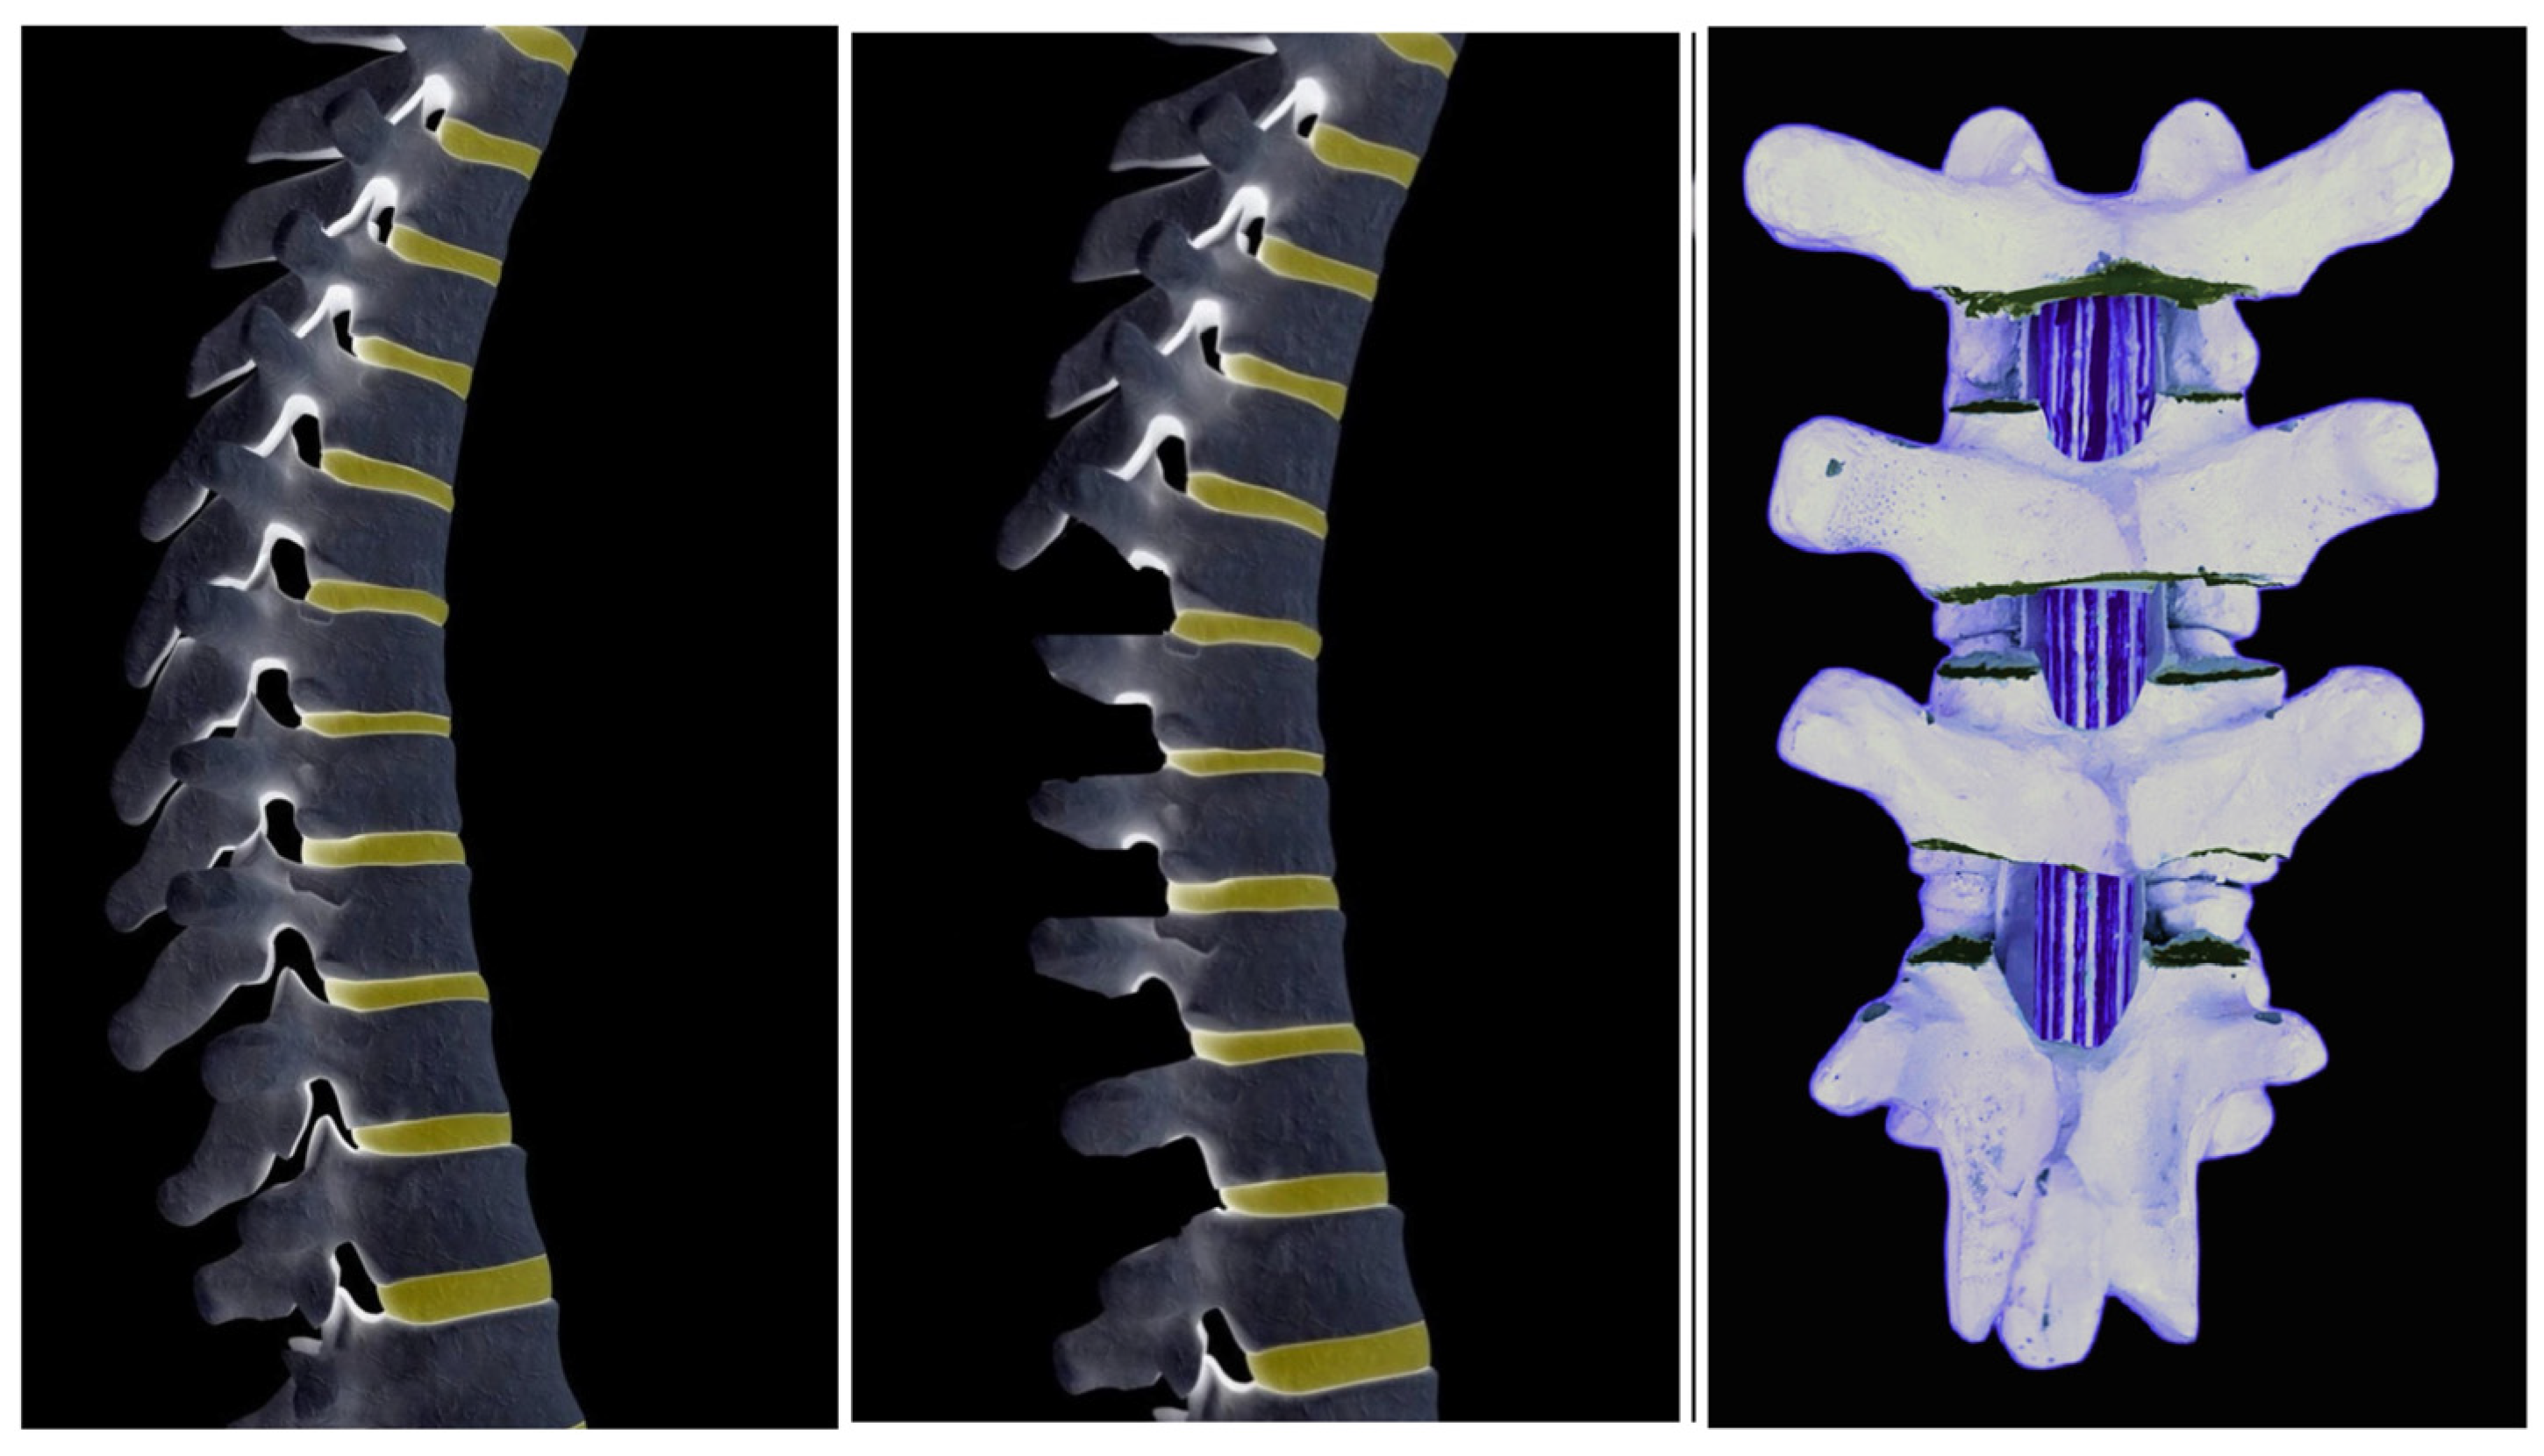

- Ponte, A.; Orlando, G.; Siccardi, G.L. The True Ponte Osteotomy: By the One Who Developed It. Spine Deform. 2018, 6, 2–11. [Google Scholar] [CrossRef] [PubMed]

- Hollyer, I.; Johnson, T.R.; Kha, S.T.; Foreman, C.; Ho, V.; Klemt, C.; Chan, C.K.; Vorhies, J.S. Introduction of a Novel Sequential Approach to the Ponte Osteotomy to Minimize Spinal Canal Exposure. Children 2023, 10, 470. [Google Scholar] [CrossRef] [PubMed]

- Gottlich, C.; Sponseller, P.D. Ponte Osteotomy in Pediatric Spine Surgery. JBJS Essent. Surg. Tech. 2020, 10, e19.00001. [Google Scholar] [CrossRef]

- Nasto, L.A.; Mousavi Nasab, S.H.; Sieczak, A.; Cattolico, A.; Ulisse, P.; Pola, E. Ponte osteotomies for treatment of spinal deformities: They are not all made equal. Eur. Spine J. 2024, 33, 2787–2793. [Google Scholar] [CrossRef]

- Pérez-Grueso, F.S.; Cecchinato, R.; Berjano, P. Ponte osteotomies in thoracic deformities. Eur. Spine J. 2015, 24 (Suppl. S1), S38–S41. [Google Scholar] [CrossRef] [PubMed]

- Holewijn, R.M.; Schlösser, T.P.; Bisschop, A.; van der Veen, A.J.; Stadhouder, A.; van Royen, B.J.; Castelein, R.M.; de Kleuver, M. How Does Spinal Release and Ponte Osteotomy Improve Spinal Flexibility? The Law of Diminishing Returns. Spine Deform. 2015, 3, 489–495. [Google Scholar] [CrossRef]